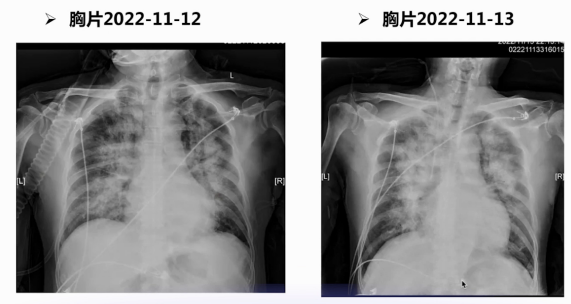

入院第六天,患者突发呼吸困难,心率105次/分,呼吸频率22次/分,血压降至89/48 mmHg,脉搏氧饱和度在鼻导管吸氧5 L/min下仅90%,双肺满布干湿啰音,血气分析提示pH 7.33、二氧化碳分压38 mmHg、氧分压62 mmHg。胸片显示双肺呈明显肺水肿表现,心电图可见V4-V6导联T波高尖,心肌损伤标志物未提示CK-MB进一步升高,白细胞、血红蛋白、血钾及肝肾功能无明显异常,仅低密度脂蛋白胆固醇轻度升高。床旁超声心动图因声窗不清,仅见后侧壁室壁节段性运动异常、心脏射血分数45%-50%、二尖瓣反流,但未明确病因。